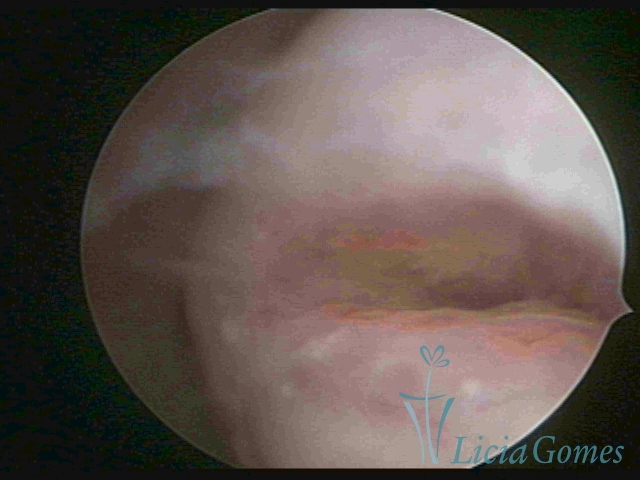

Segunda porção ou setor médio

No terço ou setor médio do canal cervical perdemos o detalhe das papilas, sendo possível a visualização de pregas e criptas. Normalmente observamos os sulcos longitudinais, que são os tecidos mais compactos, com a superfície mais vascularizada, cujos vasos seguem o seu trajeto.